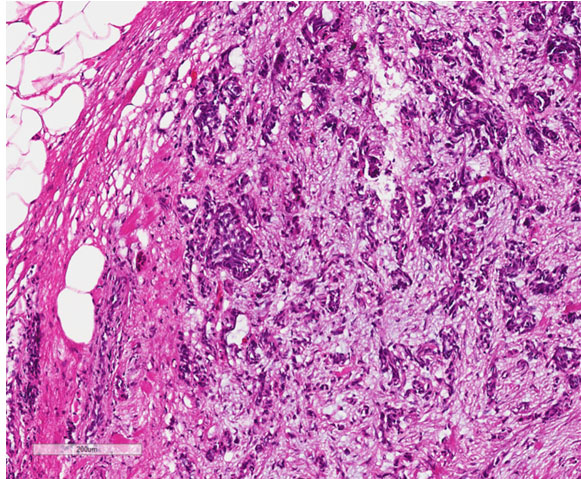

Final pathology of the retroperitoneal mass revealed uterine papillary serous carcinoma (UPSC, Figure 2). The hysterectomy specimen showed mixed serous and endometrioid carcinoma, 3.2 cm in size, invading the full thickness of the myometrium, serosa, and surface of bilateral ovaries. Pelvic and para-aortic nodes were positive. Pathology suggested that the high-grade serous component of the mixed EC had metastasized lymphatically to cause the external compression of the duodenum. Due to complete obstruction, the patient required enteral feeding postoperatively. Postoperative chemotherapy plan consisted of Carboplatin AUC6, Taxol 175 mg/m2 on a standard 21-day cycle. However, the patient experienced rapidly progressive disease limiting her therapy. She entered hospice care within three months of surgery and passed.

Figure 2: H&E staining of duodenal surface metastasis with high-grade nuclei consistent with endometrial serous carcinoma (10× magnification).